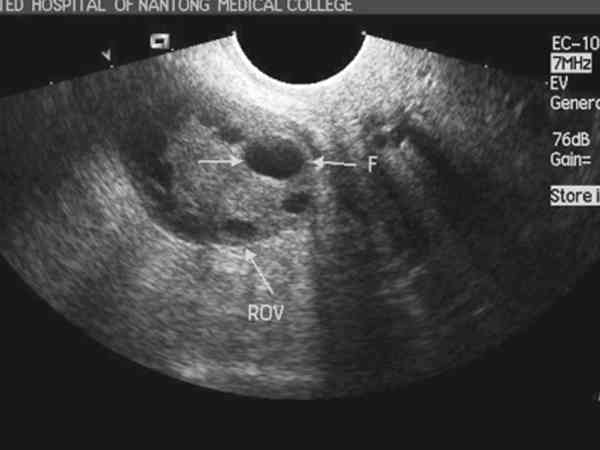

兩個卵泡一大一小是否會排出來,需要根據具體情況進行綜合判斷。如果女性處於排卵期,可能會排出。如果女性並未處於排卵期,可能不會排出。兩個優勢卵泡一大一小可能會先後都排出,也可能只排出一個,還有可能都不排出。卵泡一大一小怎麼排出並無特定規律,因為影響排卵的因素較多,需結合卵泡大小、前後檢查結果對比以及優勢卵泡發育成熟時的體內激素水平等因素來判斷是否能排卵,後面也要做B超來觀察兩個優勢卵泡是否都排出,或者是沒排出萎縮了。關於兩個卵泡一大一小排出情況,可以看看其他患者的經歷: